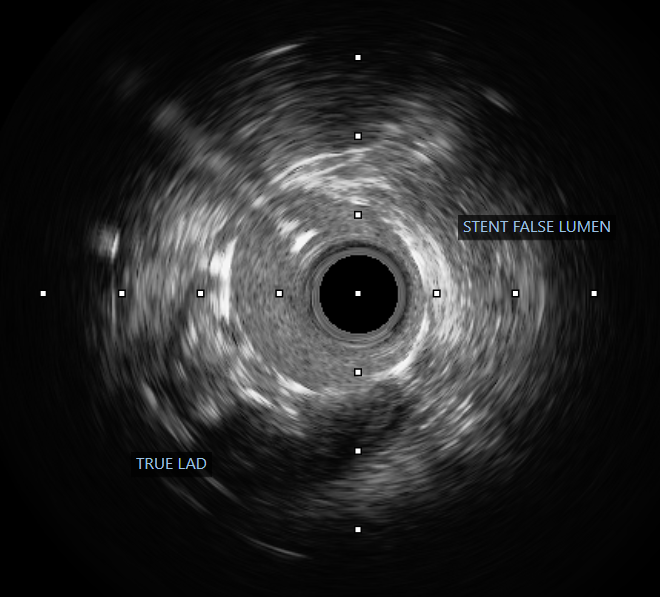

The procedure was performed via a 6 French femoral approach. The LAD was wired using a BMW guidewire and pre-dilated sequentially with non-compliant balloons sized 2.5 ¡¿ 15 mm and 3.0 ¡¿ 15 mm, achieving satisfactory lumen expansion. Considering the diffuse nature of the lesion, a DCB-only strategy was selected to avoid multiple overlapping stents. DCB angioplasty was carried out, sized 2.5 ¡¿ 30 mm and 3.0 ¡¿ 25 mm, each inflated for 60 seconds. The final angiogram revealed mild vessel recoil and a non–flow-limiting dissection with TIMI 3 flow. To optimize the result, the operator attempted re-wiring for bailout stenting; however, the guidewire inadvertently entered a false lumen. Despite this, pre-dilatation was performed followed by deployment of a 2.5 ¡¿ 26 mm Onyx drug-eluting stent from the mid to distal LAD. Subsequently, the vessel flow deteriorated to TIMI 0. Intravascular ultrasound confirmed subintimal stent placement with a long false lumen extending from the mid LAD before the septal branch. Multiple attempts to re-enter the true lumen, both proximally and distally, were unsuccessful. The patient developed chest discomfort, which was partially relieved with morphine. In view of persistent LAD occlusion, intra-aortic balloon pump (IABP) support was initiated for hemodynamic stabilization, and the patient was referred for urgent coronary artery bypass grafting (CABG).

Case Summary